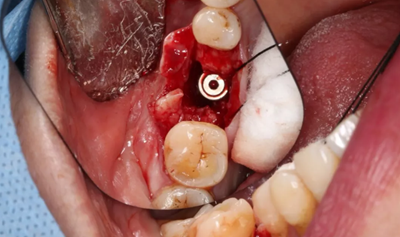

12、延期種植手術(shù)過程

使用直徑3mm的環(huán)形取骨鉆切取長約9mm的柱狀骨標(biāo)本,用于組織學(xué)和顯微影像檢查

(攝于2017年4月14日)

由于取骨致窩洞較大,加之缺牙間隙大,只好選擇植入5mm直徑種植體;種植備洞完成后,頰側(cè)骨壁厚度僅約1mm。

植入國產(chǎn)威高(WEGO)5.0×11mm種植體,檢查種植體位于理想軸位。